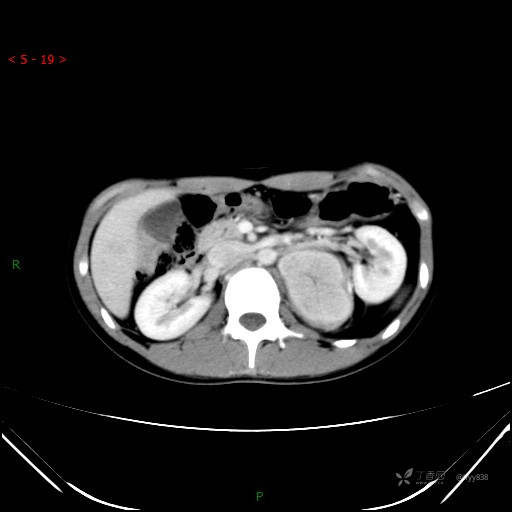

增强动脉期